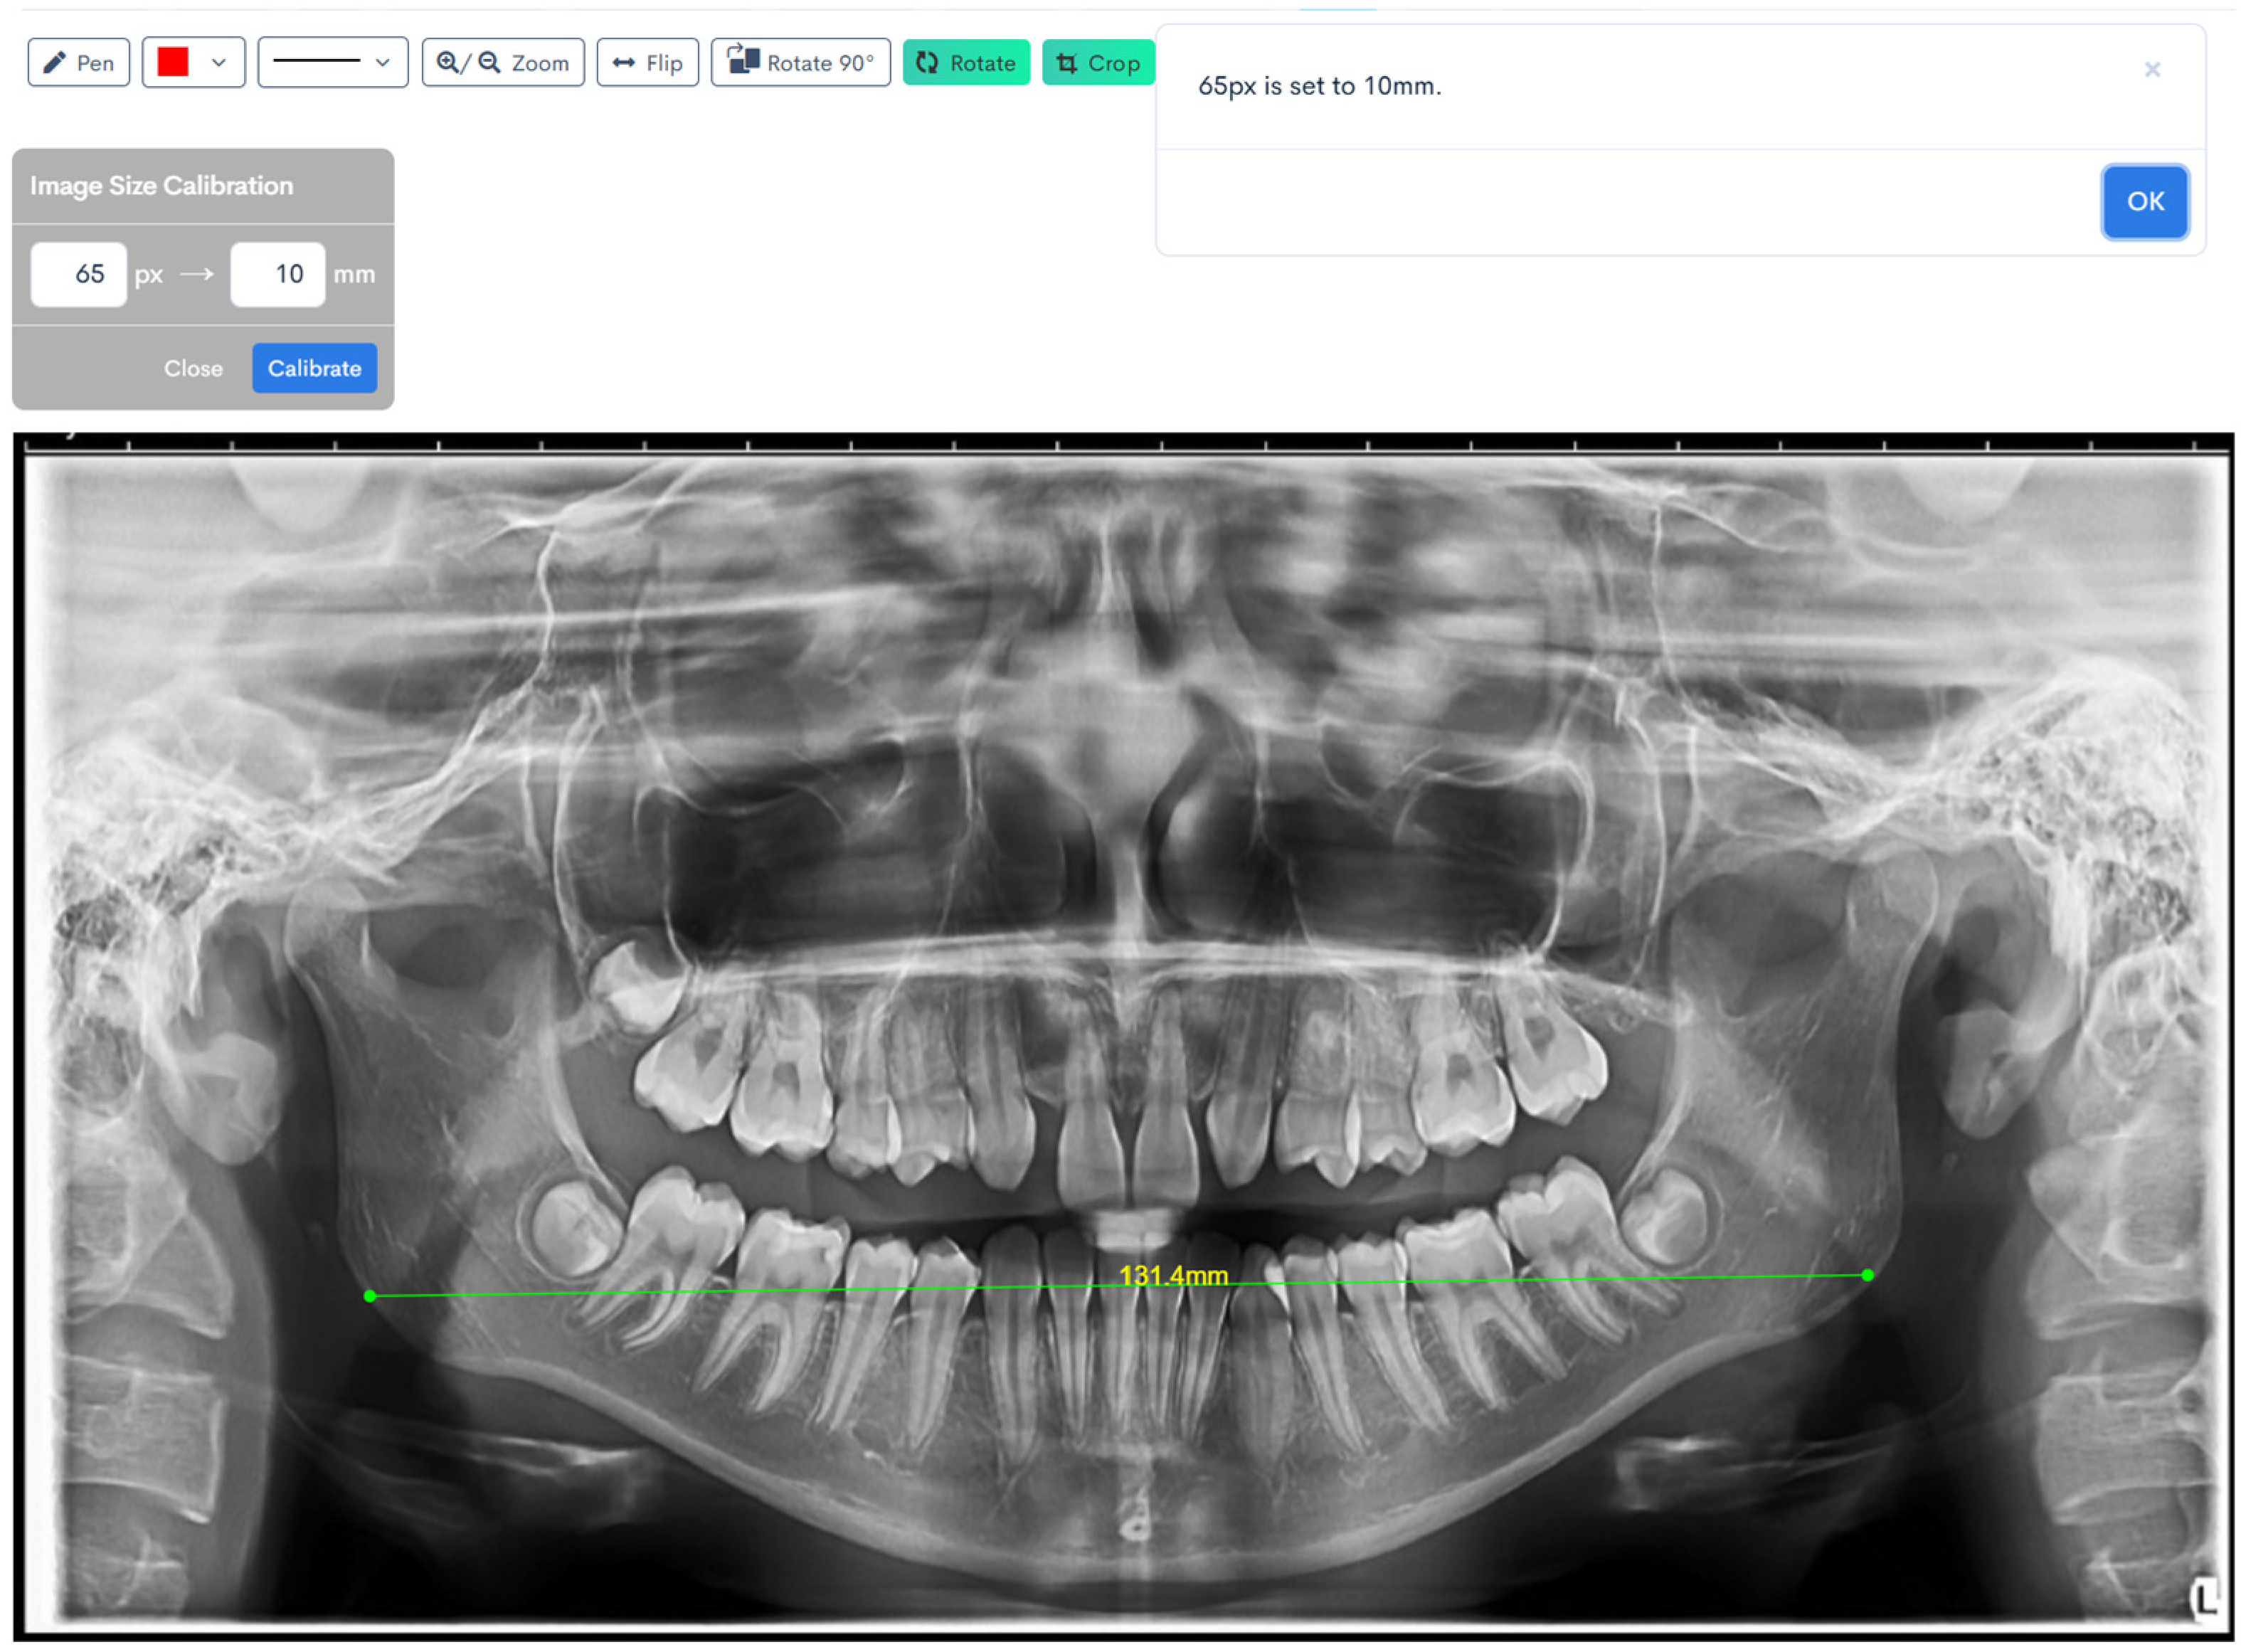

Figure 1, Figure 2, Figure 3, Figure 4, Figure 5 and Figure 6 illustrate the AI-assisted digital measurements exported from the WebCeph software, showing the identification of anatomical landmarks and linear or angular dimensions analyzed in this study.

Digital tracing of bigonial width performed on WebCeph using a panoramic radiograph. The measurement represents the horizontal distance between the right and left gonion points (Go), shown by the green line with an on-screen readout of 131.4 mm (Figure 5).

Figure 5. Bigonial Width Digital Tracing on WebCeph. The green line connects the automatically detected bilateral gonion (Go) points, showing the measured bigonial width (mm). Note: Images represent direct screenshots exported from the WebCeph AI platform. Landmarks and measurement lines were automatically generated and manually verified by the authors.